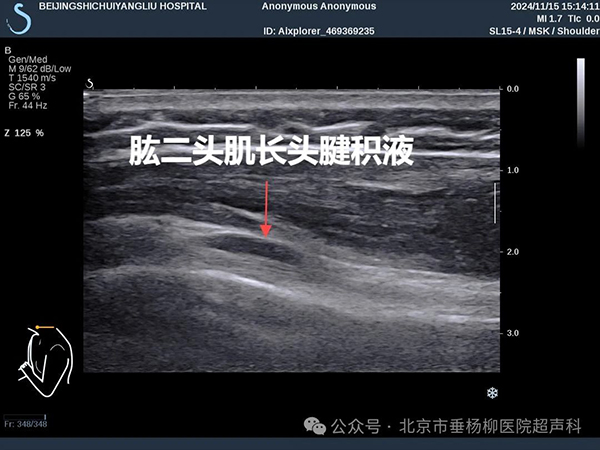

⑥肌腱积液、钙化